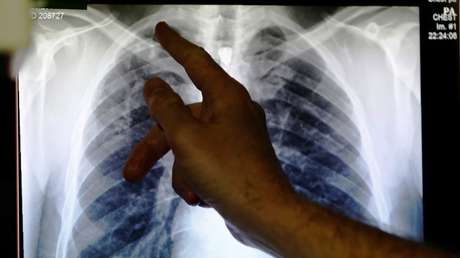

Según informa el portal Science Alert, la anciana acudió al Centro Hospitalar Universitário de Lisboa Central por presentar dificultades respiratorias moderadas y dolor agudo en el pecho. Una radiografía reveló que la parte inferior de su pulmón derecho había sangrado. A la paciente se le diagnosticó un neumotórax, lo que comúnmente se conoce como 'pulmón colapsado'.